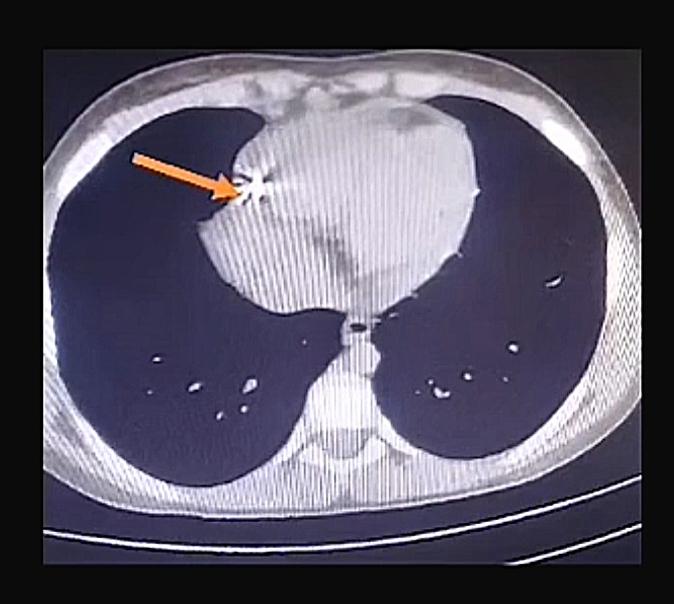

وعلى الفور، تولى الفريق الجراحي بقيادة الأستاذ الدكتور حسام فتحي علي، رئيس وحدة حوادث جراحة القلب والصدر، إجراء عملية استكشاف عاجلة للصدر، حيث تبين وجود تهتك بالرئة اليمنى واختراق المسمار للغشاء التموري وإصابة القلب إصابة مباشرة تسببت في نزيف داخلي حاد حوله، وبمهارة فائقة تم استخراج المسمار وإصلاح التهتكات والسيطرة على النزيف بالكامل.